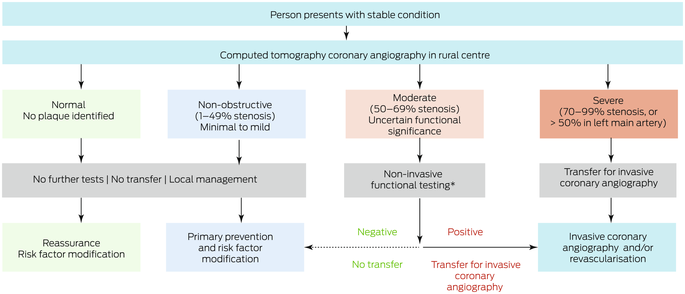

Computed tomography coronary angiography (CTCA) is a non‐invasive imaging modality for comprehensively evaluating the burden and severity of CAD.6 CTCA can detect high risk plaque and assess lesion‐specific ischaemia using the standard acquisition and computed tomography (CT)‐derived fractional flow reserve (CT‐FFR) respectively.6,7 Making CTCA available in rural centres with 64‐slice (or better) CT scanners (, figure 1) would improve access to cardiac services.8 CTCA could also identify people with non‐obstructive CAD who do not require transfer to metropolitan hospitals for ICA. However, the costs of establishing CTCA facilities in rural Australia have not been evaluated.6

Alternative care model: local computed tomography coronary angiography

We also examined a potential alternative model of care for which we assumed that CTCA could be performed in rural centres (Box 1). People with normal or non‐obstructive CAD (< 50% stenosis) according to CTCA would not require ICA and consequently not be transferred to metropolitan hospitals, but those with severe CAD (≥ 70% stenosis) would be transferred. People with moderate CAD (50–69% stenosis) would undergo functional testing (stress echocardiography or CT‐FFR) in the rural centre; for the functional testing outcome we used the actual revascularisation outcome. We compared health care costs for usual care (ie, as determined by retrospective review of medical records) and for the alternative care model (simulated rural CTCA results based on individuals’ actual ICA findings).

Box 1 – Alternative care model: local computed tomography coronary angiography for people in rural or remote areas of Western Australia

* Stress echocardiography or computed tomography‐derived fractional flow reserve (CT‐FFR).